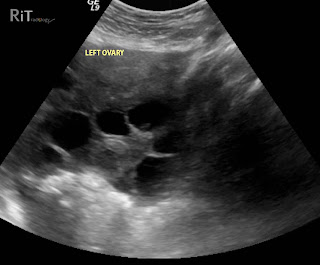

Ultrasound images show enlarged ovaries with multiple cysts in a woman who had received assisted reproduction procedure. Ascites is also present but not shown on these images.

- Enlarged ovaries with several cysts

- Necklace sign (string of ovarian follicles close to the surface of the ovary) may indicate an increased risk of developing this syndrome